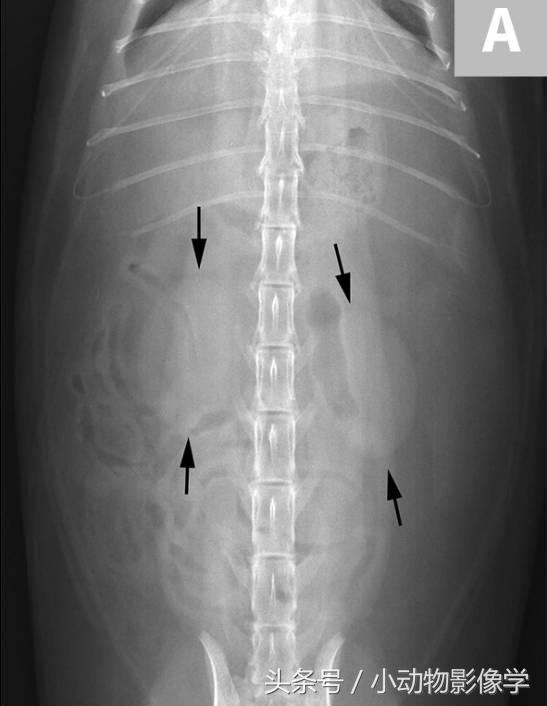

图1A、用于观察肾脏(箭头处)的正常猫的腹背位X光片。我们要记住肾脏的豆形外观,平滑的囊状边缘,正常大小(约L2腰椎长度的2.2倍)和位置。由于这只猫腹膜后脂肪的量较少,所以两侧肾脏都容易看到。犬的左肾比右肾更容易识别和评估,因右肾边缘的前侧顶点模糊了肝尾叶的肾窝。